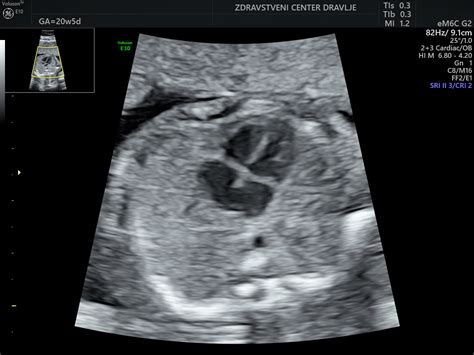

Četrti pregled (20. - 22. teden nosečnosti): Ta pregled predstavlja eno najpomembnejših ultrazvočnih preiskav v nosečnosti - natančno ultrazvočno oceno morfologije ploda. Namenjena je predvsem potrditvi normalnega razvoja ploda, odkrivanju večjih razvojnih nepravilnosti ter t.i. mehkih označevalcev, ki lahko povečajo tveganje za kromosomske napake. Ob koncu tega obdobja so plodovi organi večinoma razviti, kar omogoča z veliko verjetnostjo napoved zdravega otroka. Izjema so pljuča in možgani, katerih razvoj se nadaljuje tudi po rojstvu, zato je nevrološka ocena v tej fazi manj zanesljiva.

Nadaljnje ultrazvočne preiskave: Med 19. in 23. tednom nosečnosti se opravi morfološki ultrazvok, ki je bistven za oceno plodovih organov. Po presoji ginekologa se lahko opravijo dodatni ultrazvočni pregledi med 35. in 37. tednom, še posebej če obstajajo posebne potrebe ali tveganja, kar omogoča tudi dodatno kontrolo rasti in morfologije, saj nekatere razvojne nepravilnosti postanejo vidne šele v kasnejših obdobjih nosečnosti.